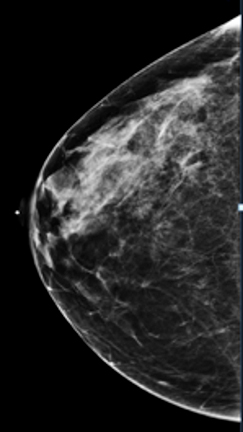

Compare these two images. You can see the benefits of 3D tomosynthesis. A small cancer (circled) on tomosynthesis slices in image A (left) is not apparent in the standard 2D mammogram, image B (right) of the same patient and same projection.